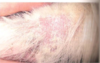

What is the treatment protocol for rabbit spirochetosis (“rabbit syphylis”)?

long acting penicillin

Procaine+ Benzathine Pen G or Combi-pen, give 2 SQ doses 4 days apart

Spirochetosis - “Rabbit Syphilis” (aka Vent Disease)

- Treponema canuculi venereal from doe to kit during parturition.

- Dz of young rabbits à scabs on nose and vent.

- Dx: Biopsy, PCR, treatment response

- Tx: Long acting penicillin injection – Procaine + Benzathine Pen G or Combi-pen, give 2 SQ doses 4 days apart